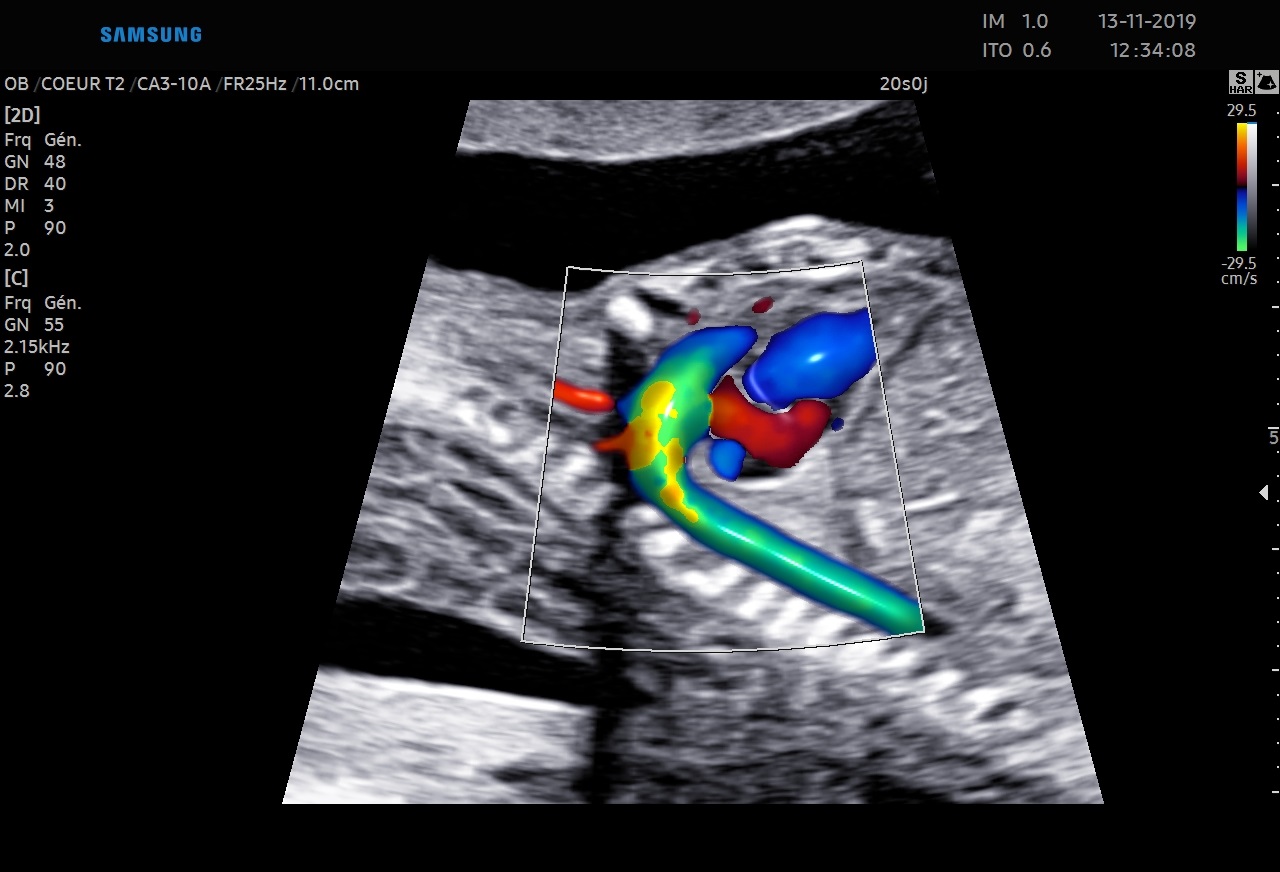

5D Heart™ est un outil intelligent permettant d’établir un diagnostic cardiaque fiable grâce à la visualisation des 9 coupes essentielles, recommandées par les sociétés internationales. Couplé à l’analyse des échanges vasculaires cardiaques, il rend l’examen du cœur plus intuitif indépendamment de la position du fœtus.